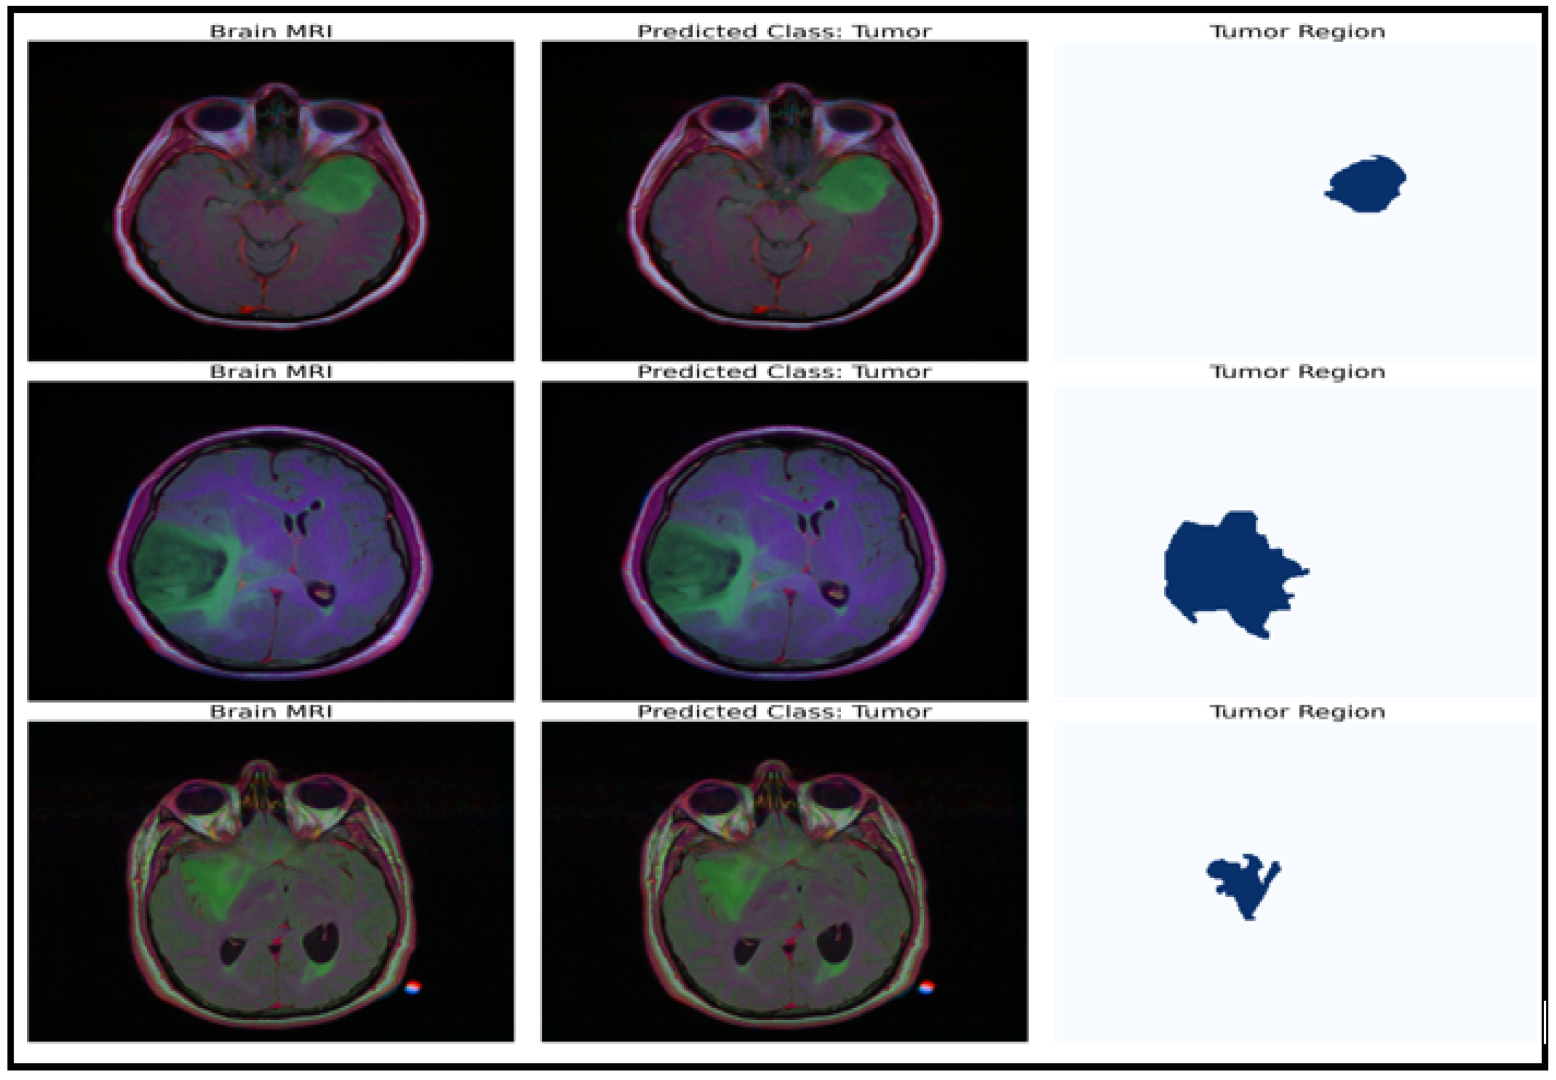

The model can be used for brain tumor segmentation. The result of the U-Net architecture is a probability map representing the likelihood of each pixel in the input image belonging to the tumor region. A threshold can be set on this map to obtain the binary segmentation map, which indicates the presence or absence of the tumor in each pixel of the input image. The binary segmentation map obtained from the U-Net can be used to improve the accuracy of the brain tumor detection and classification tasks performed by the CNN model with fine-tuned ResNet50. For example, the binary segmentation map can focus the proposed model’s attention on the tumor region, reducing false positives and improving the overall accuracy. To integrate the outputs from the CNN model with fine-tuned ResNet50 and the U-Net architecture, the binary segmentation map can be overlaid onto the input MRI image to highlight the tumor region. Figure 7 shows the segmentation results for a selected tumor region, while Figure 8 shows the results for a non-tumor region. This combined approach can provide valuable insights for clinical diagnosis and treatment planning.

Figure 7.

Dataset classification and model prediction of tumor regions.